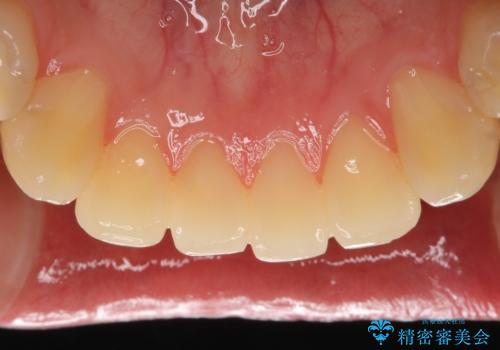

不適なレジン充填によるデコボコがなくなったことで歯磨きしやすくなり、また気にされていた咬み合わせも良くなり、ご満足頂けました。

クラウンの種類:オールセラミッククラウン スタンダード

シェード:NW0